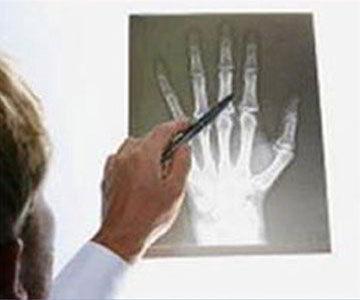

¿Te duelen los huesos o articulaciones?

Tratamientos efectivos para problemas de osteoartritis

¿Sientes dolor al caminar o al realizar alguna

actividad?

El Dr. José Manuel Aguilera Zepeda, es el indicado para tratar cualquier problema que tengas con los huesos o articulaciones. Está ubicado en la delegación Tlalpan, Ciudad de México.

Como médico ortopedista, el Dr. José Manuel Aguilera Zepeda se especializa en cirugía ortopédica, con enfoque en osteoartritis, artroplastia total de cadera (prótesis de cadera), y artroplastia total de rodilla (prótesis de rodilla).